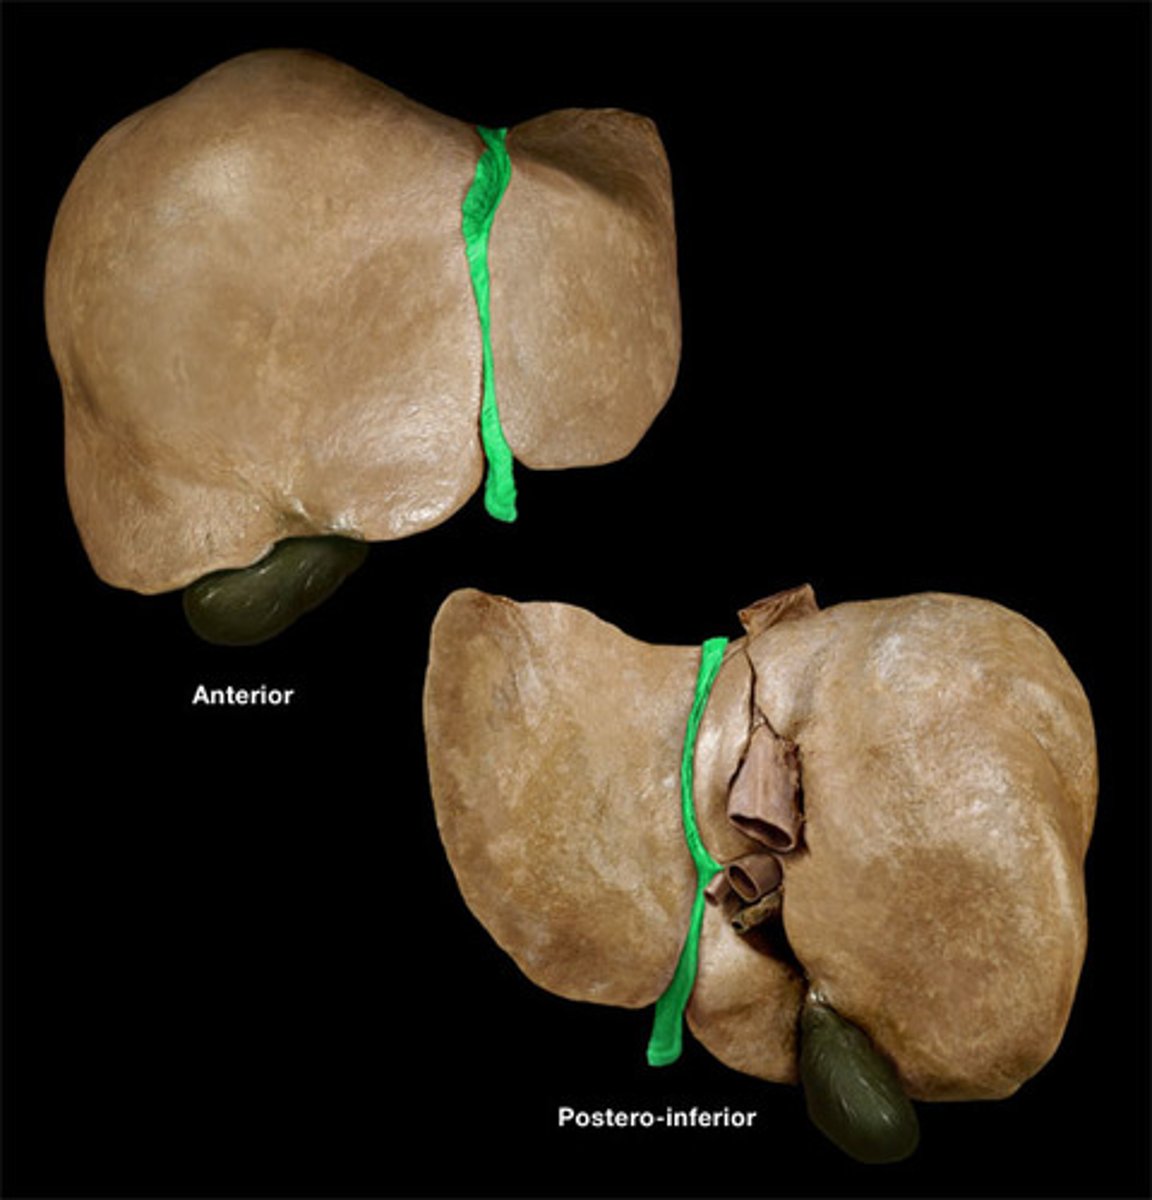

falciform ligament

right lobe (of liver)

left lobe (of liver)

quadrate lobe (of liver)

caudate lobe (of liver)

diaphragmatic surface (of liver)

bare area (of liver)

round ligament of liver